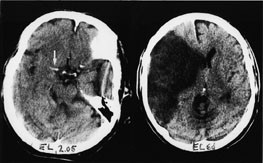

De følgende eksempler er hentet fra pasienter innlagt i Nevrologisk avdeling, Haukeland Sykehus, med akutt cerebral iskemi og undersøkt med CT innen tre timer og ti minutter etter symptomdebut (bildet til venstre, fig 1 – 4) og med oppfølgende CT (bildet til høyre, fig 1 – 4). Bildene illustrerer de forannevnte kardinaltegn (tab 1).

Hypodensitet i insula (fig 3). Iskemi fører til vanskeligheter med å diskriminere cortex fra subkortikalt vev i insula og fører til tap av ”insula ribbon” (cortexgrensen).